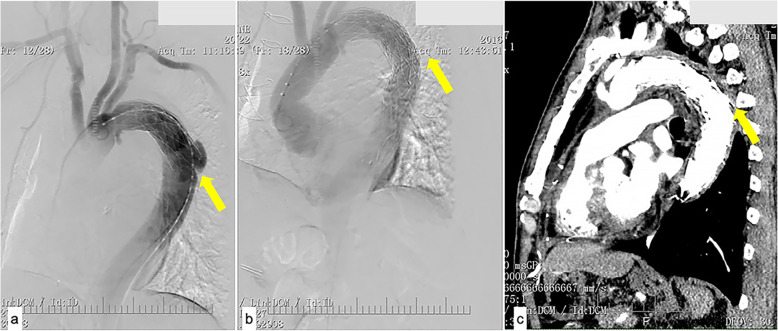

In another case, the distal part of the elephant trunk was inserted into an ulcer of the descending aorta in the first surgery (Fig. 3a). This was found by CT angiography 2 weeks after the operation. With limb malperfusion, second stage TEVAR was performed. The ulcer was covered, and the malperfusion was resolved (Fig. 3b, c).

Fig. 3.

a Angiography illustrating that the distal part of the elephant trunk was raised to an ulcer of the descending aorta. b Second-stage TEVAR covered the ulcer. c At one-month follow-up, aorta remodeling was efficient